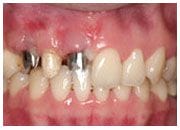

植牙過程

植入植體